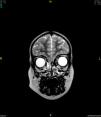

Presentamos el caso de un niño de 3 años, sin antecedentes patológicos y correctamente vacunado, remitido a nuestro hospital por meningitis bacteriana ante la posible necesidad de cuidados intensivos. La reacción en cadena de la polimerasa (PCR) multipanel realizada en su hospital de origen en líquido cefalorraquídeo fue positiva para Haemophilus influenzae (que creció en el cultivo tradicional, serotipo no tipificable) y Streptococcus pneumoniae. Ante la sospecha de coinfección meníngea por 2 microorganismos se realizó estudio inmunitario, que resultó normal, y resonancia magnética nuclear (RMN) cerebral, que objetivó un encefalocele frontoetmoidal derecho (fig. 1). El paciente evolucionó favorablemente del proceso infeccioso agudo. Posteriormente se realizó la intervención neuroquirúrgica del encefalocele, mediante reintroducción del parénquima herniado y reparación de la pared del seno frontal.